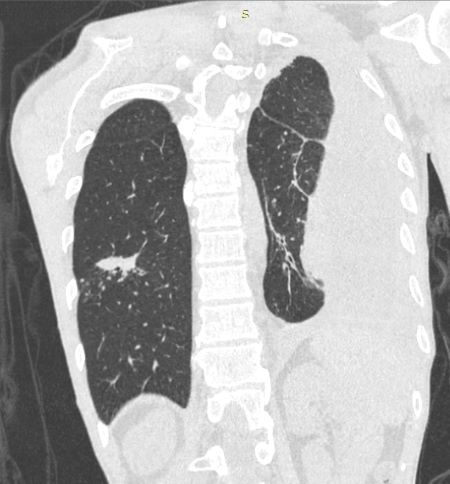

При исследовании в верхушке левого лёгкого было выявлено, субплеврально, полостное образование с толстыми стенками (толщиной до 3,5 мм) с нечёткими и неровными контурами, с прилежанием к костальной плевре на широком основании, размерами 26х22 мм. Вокруг данного образования определялся участок консолидации с прослеживающимися, суженными, деформированными просветами бронхов. Каудальнее образования и участка консолидации определялись хаотично расположенные очаги размером до 7 мм. В S1-2 левого лёгкого субплеврально определялось округлое образование с чёткими, неровными контурами с прилежанием к костальной плевре, размером до 11 мм. В левой плевральной полости жидкостное содержимое с максимальной сепарацией листков плевры до 54 мм, на этом фоне листки плевры были уплотнены, утолщены до 7 мм. На фоне жидкостного содержимого в плевральной полости, в паренхиме левого лёгкого отмечались множественные линейные фиброзные тяжи. В S6, S9 правого лёгкого, перибронховаскулярно, определялись множественные очаги по типу «дерева в почках» (размером до 6 мм), сливающиеся между собой с формированием участка консолидации размером до 27 мм. Кроме того, в правом лёгком определялись множественные мелкие центрилобулярные и субплеварльные очаги уплотнения размером до 4 мм.

Отмечался перелом переднего отрезка 5-го ребра справа с формированием диастаза между отломками до10 мм. В окружающих мягких тканях мелкие костные структуры размером до 2 мм.Заключение

С учетом анамнеза и данных МСКТ-исследования было вынесено заключение КТ-картины полостного образования в верхушке левого лёгкого, с наличием участка консолидации, очагов отсева в верхней доле левого лёгкого, субплеврального образования в верхней доле левого лёгкого, левостороннего плеврального выпота, с признаками утолщения листков плевры, фиброзных изменений левого лёгкого, очагов по типу «дерева в почках» с формированием участка консолидации в нижней доле правого лёгкого (данные изменения, вероятно, соответствуют проявлениям вторичного туберкулёза, дифференцированного с периферическим образованием с признаками вторичных изменений. Перелом переднего отрезка 5-го ребра справа.